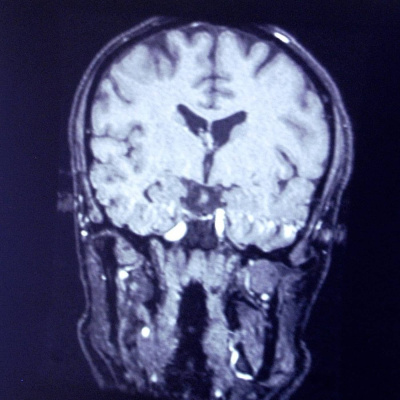

Det har varit snökaos på vägarna i södra Sverige. Det norska stortinget har bombhotats. Och så hör vi om forskning om ljud och ljus som kan hjälpa personer som har demenssjukdomen Alzheimers. Lyssna på alla avsnitt i Sveriges Radio Play.